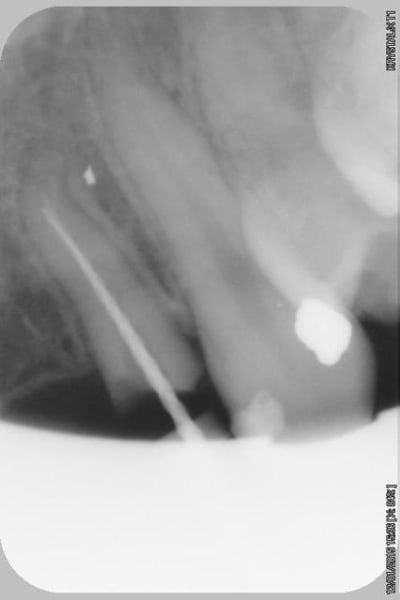

le scan n'est pas terrible, mais suffisant pour voir que 22 une fois extraite, ne va pas etre simple à implanter, par contre 11/21 avec un peu d'expansion...

Des lecross section21 jinha0 - Eugenol

Des lecross section sf6tbl - Eugenol

Des le cross section 12 vyz5ug - Eugenol

Des le cross section 22 w31w6b - Eugenol